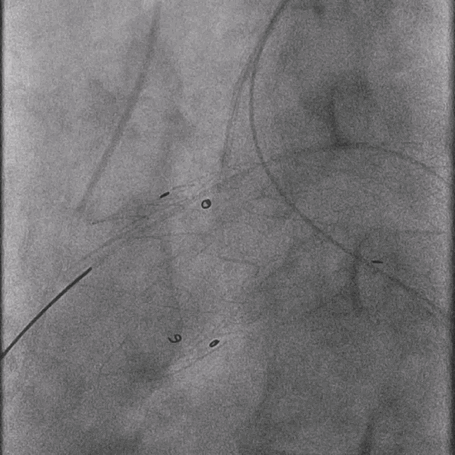

03. 左侧肱动脉采用0.035"泥鳅导丝硬头配合支撑导管顺利破膜,引入4mm球囊予以开窗处扩张。

泥鳅导丝怎么用曲乐丰教授团队:0.018"和0.035"普通泥鳅导丝行胸主动脉弓上分支原位开窗的病例分享_https://www.jmylbn.com_新闻资讯_第31张

调节支撑导管垂直于覆膜

泥鳅导丝怎么用曲乐丰教授团队:0.018"和0.035"普通泥鳅导丝行胸主动脉弓上分支原位开窗的病例分享_https://www.jmylbn.com_新闻资讯_第32张

泥鳅导丝硬头顺利破膜